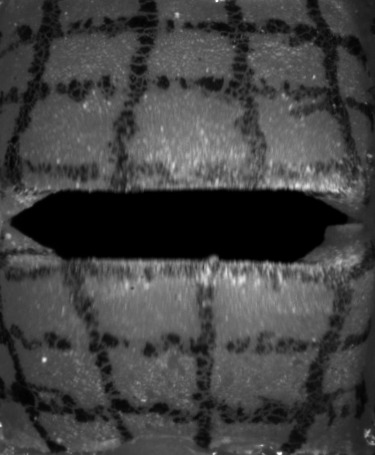

High-speed Camera

The high-speed camera provides a sequence of mono-chromatic images, as shown in Fig. 3. These images can be described as a function of intensities with an image resolution , the screen-space coordinates and with being the currently sampled frame of the video with many frames in total. Then, and denote the estimated motion of the screen-space coordinate at time along the longitudinal and lateral axis, respectively, resulting in the motion vector field:

We applied the sparse to dense optical flow algorithm based on the Lucas-Kanade feature tracker with pyramids by [25], which is available in OpenCV [26]. Such dense optical flow algorithm estimates a motion for every pixel of the input image, but tends to oversmooth flows (see Fig. 4(a)), which produces artifacts at edges. To mitigate this problem, we apply a mask (see Fig. 4(b)), which helps to distinguish the vocal folds from the gap between them. We use the intensity values for the mask segmentation with a subsequent median filter for more robustness to noise. Using the mask (see Fig. 4(c)), we set the motion vectors inside the gap explicitly to zero vectors, since there is no vocal fold movement. For consistency with the remaining data, the motion in the image plane is converted to physical domain units. The high-speed images and the resulting optical flows are discrete in space (individual pixels) and in time (individual frames). We interpolate the resulting discrete vector piecewise bilinearly in space with continuity and we interpolate quadratically with continuity in time to extract a continuous time-dependent two-dimensional vector field.